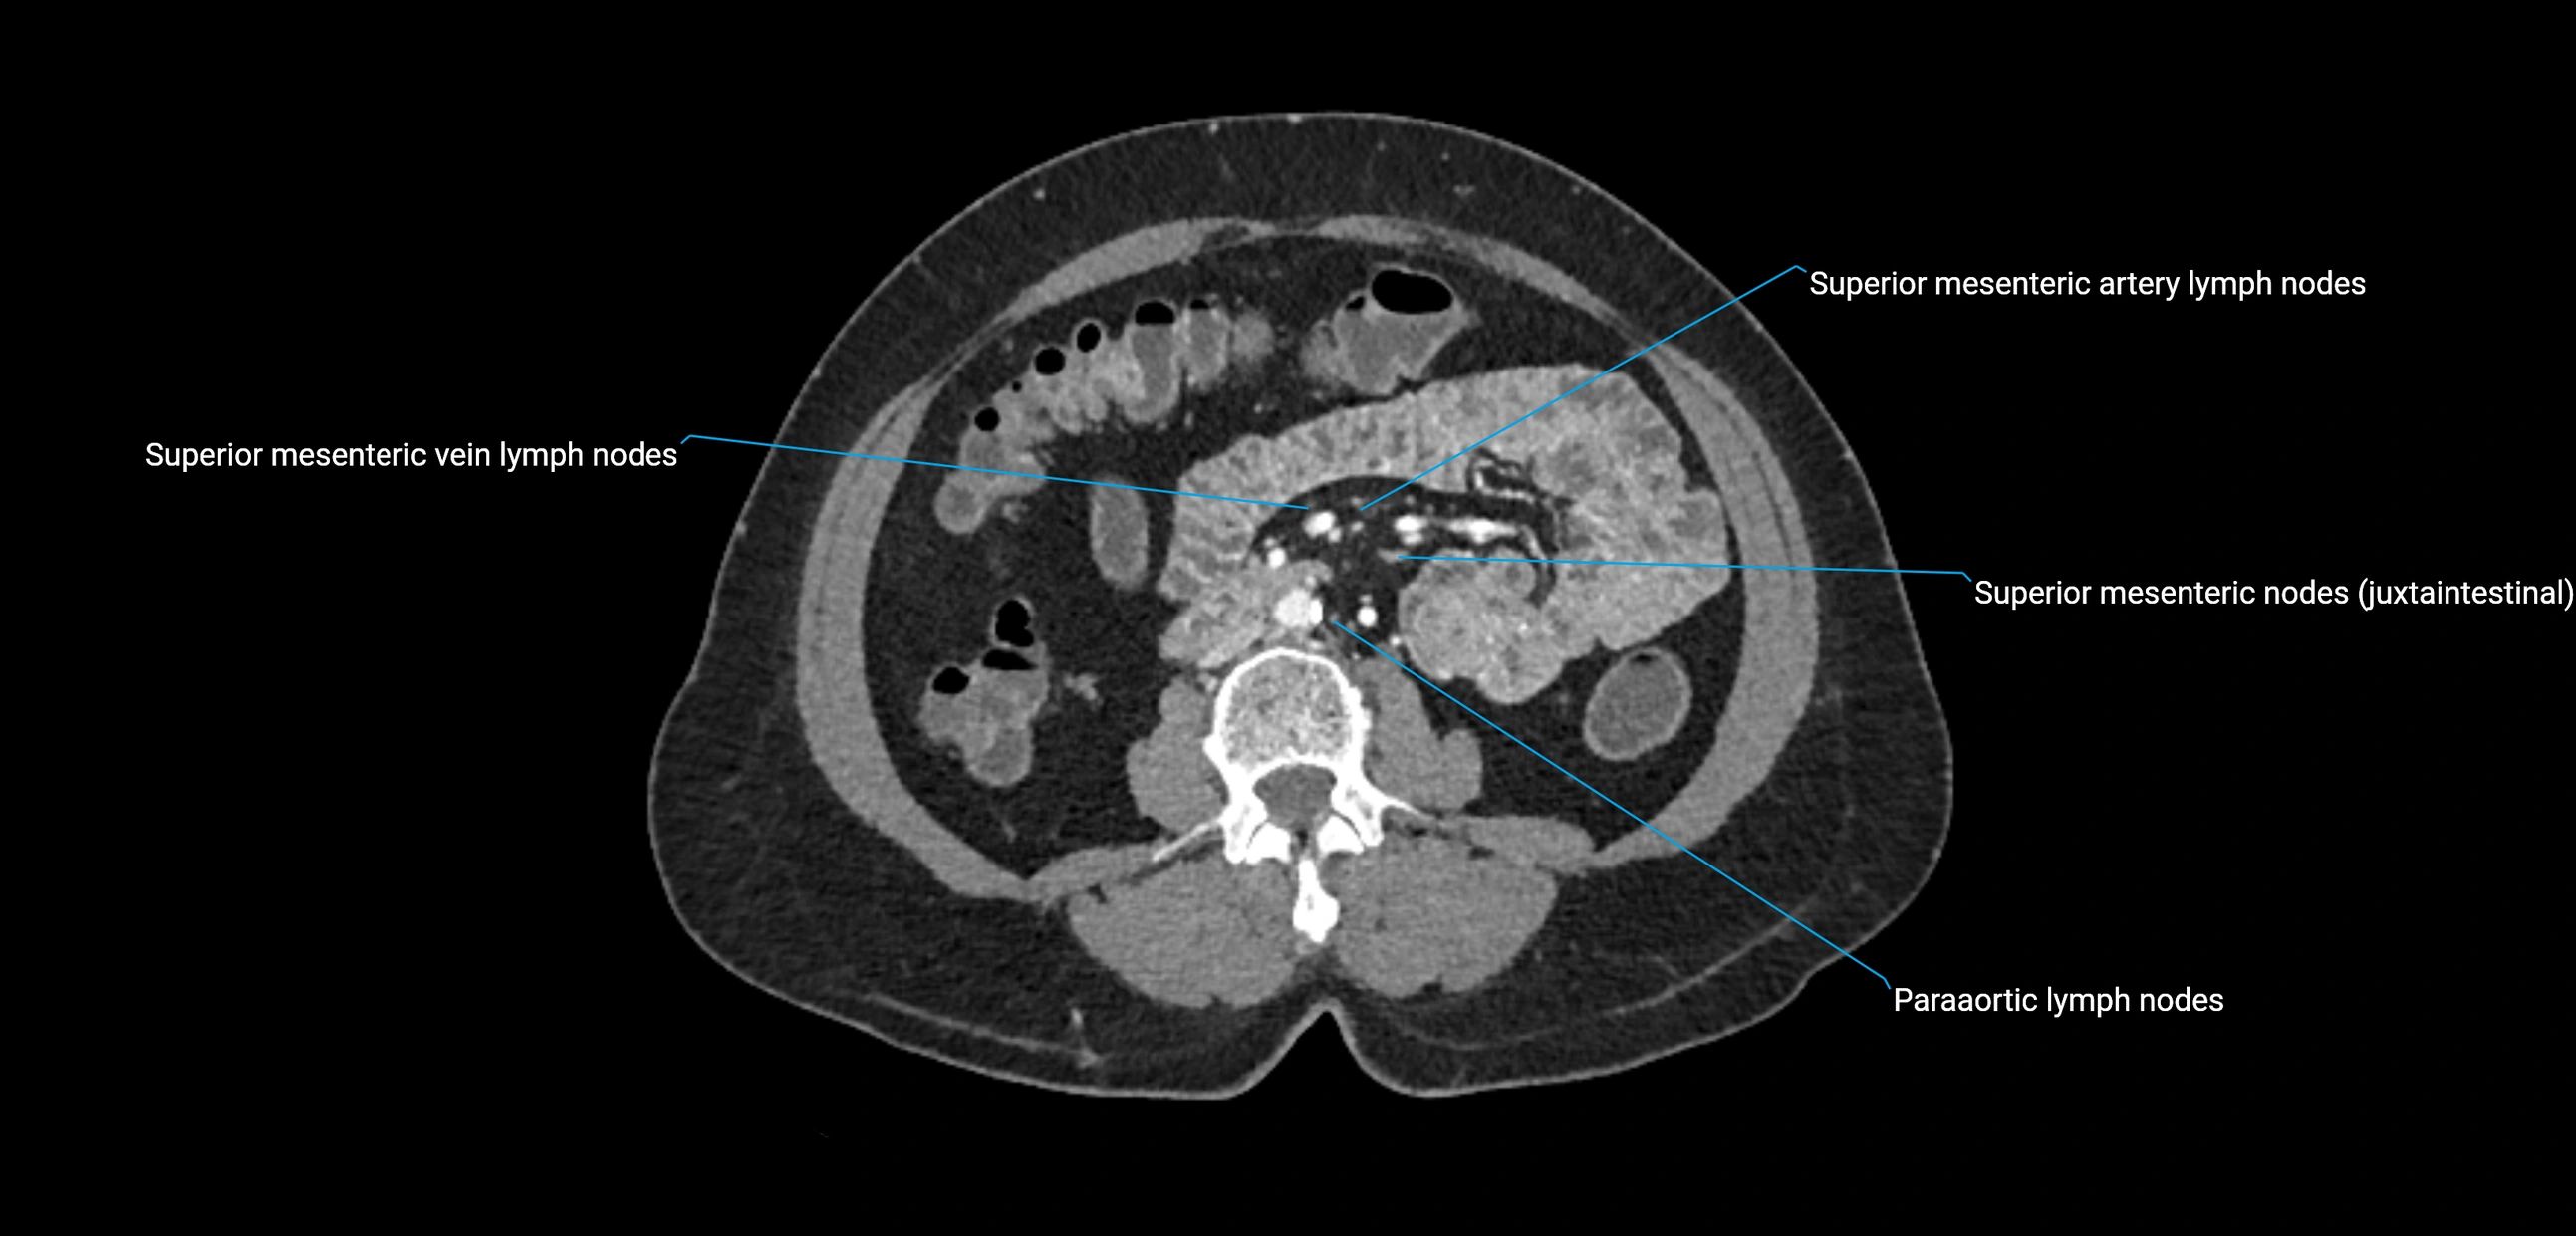

CT Appearance

CT Pre-Contrast:

• Nodes appear as soft-tissue density nodules adjacent to the aorta and IVC

• Calcification may be seen in chronic infections (e.g., tuberculosis)

CT Post-Contrast:

• Normal nodes enhance homogeneously

• Malignant nodes may show heterogeneous enhancement, central necrosis, or conglomerate formation

• Size >1 cm short axis is suspicious, though morphology and distribution are equally important